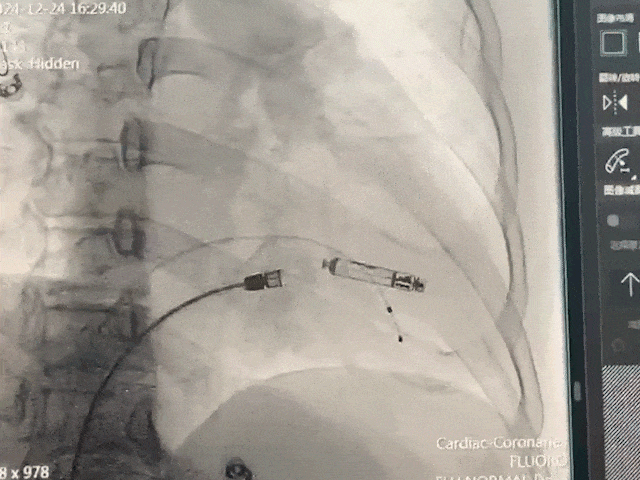

手术过程部分展示

后撤保护套筒激活无导线起搏器,调至备用起搏模式

调弯跨三尖瓣进入右室低位间隔

轻微释放调弯精确调整位置